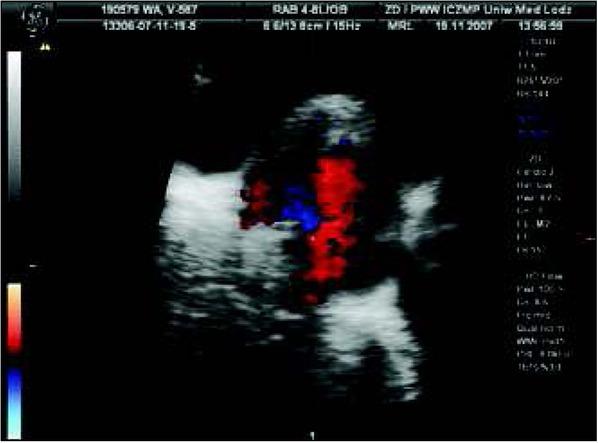

Fig. 1

Abnormal fetal heart (fetus in cephalic presentation, longitudinal position I): common atrium with left atrial appendage (LAA) on the right side of the fetal heart, single atrioventricular valve opening to single ventricle with trabeculation suggesting right ventricle.Ryc. 1. Nieprawidłowy obraz serca płodu (płód w położeniu główkowym, postawa I): szeroki dominujący przedsionek z uszkiem sugerującym uszko lewego przedsionka LAA, które leży po prawej stronie serca pojedyncza komora o typie komory prawej (RV), jedna zastawka przedsionkowo-komorowa.